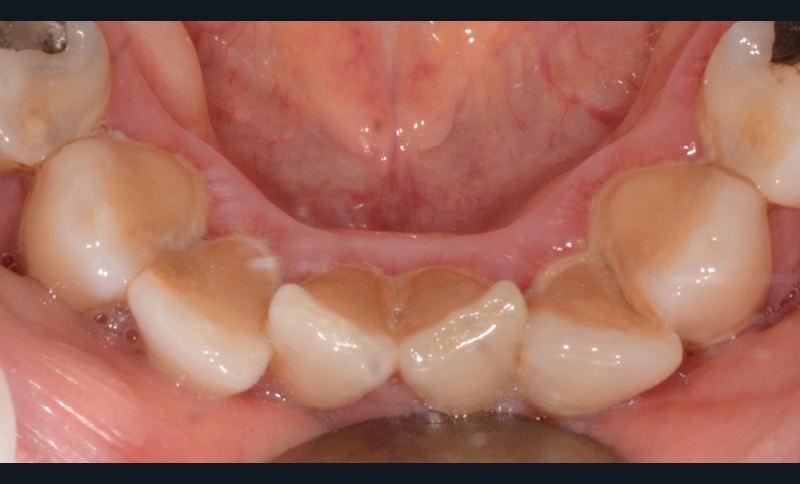

Les Drs Marie Clément et Clara Marcoux aborderont ensuite les différents apports de la dentisterie esthétique aux traitements orthodontiques. Les problèmes de dyschromies isolées ou généralisées, congénitales ou acquises seront développés ainsi que les anomalies de proportions dentaires (dents riziformes…), le maquillage (transformation d’une canine en incisive latérale…) et le remplacement des dents antérieures. Les auteurs présenteront l’intérêt du Digital Smile Design dans le diagnostic et la communication et l’arsenal thérapeutique à notre disposition pour améliorer la satisfaction de nos patients (éclaircissement, traitement des taches de l’émail, composites stratifiés, fig. 9a-d).

Le début et milieu d’après-midi seront consacrés à l’empreinte numérique, désormais utilisée pour les empreintes d’étude, les set-up, le thermoformage. Les Drs Guillaume Lecocq et Stéphane Desplanques monteront le thermoformage et comment ces empreintes numériques peuvent permettre de confectionner des appareils vestibulaires, linguaux, voire des aligneurs (fig. 1 et 2).